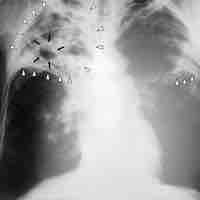

A pathogen or infectious agent is a microorganism such as a virus, bacterium, prion, or fungus that causes disease in its host.